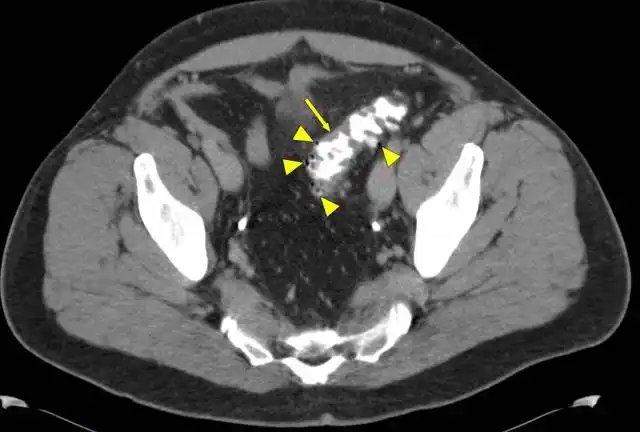

腹部ct在骨盆水平的腹部ct轴位图像:多发憩室和肠壁增厚(箭头)结肠镜